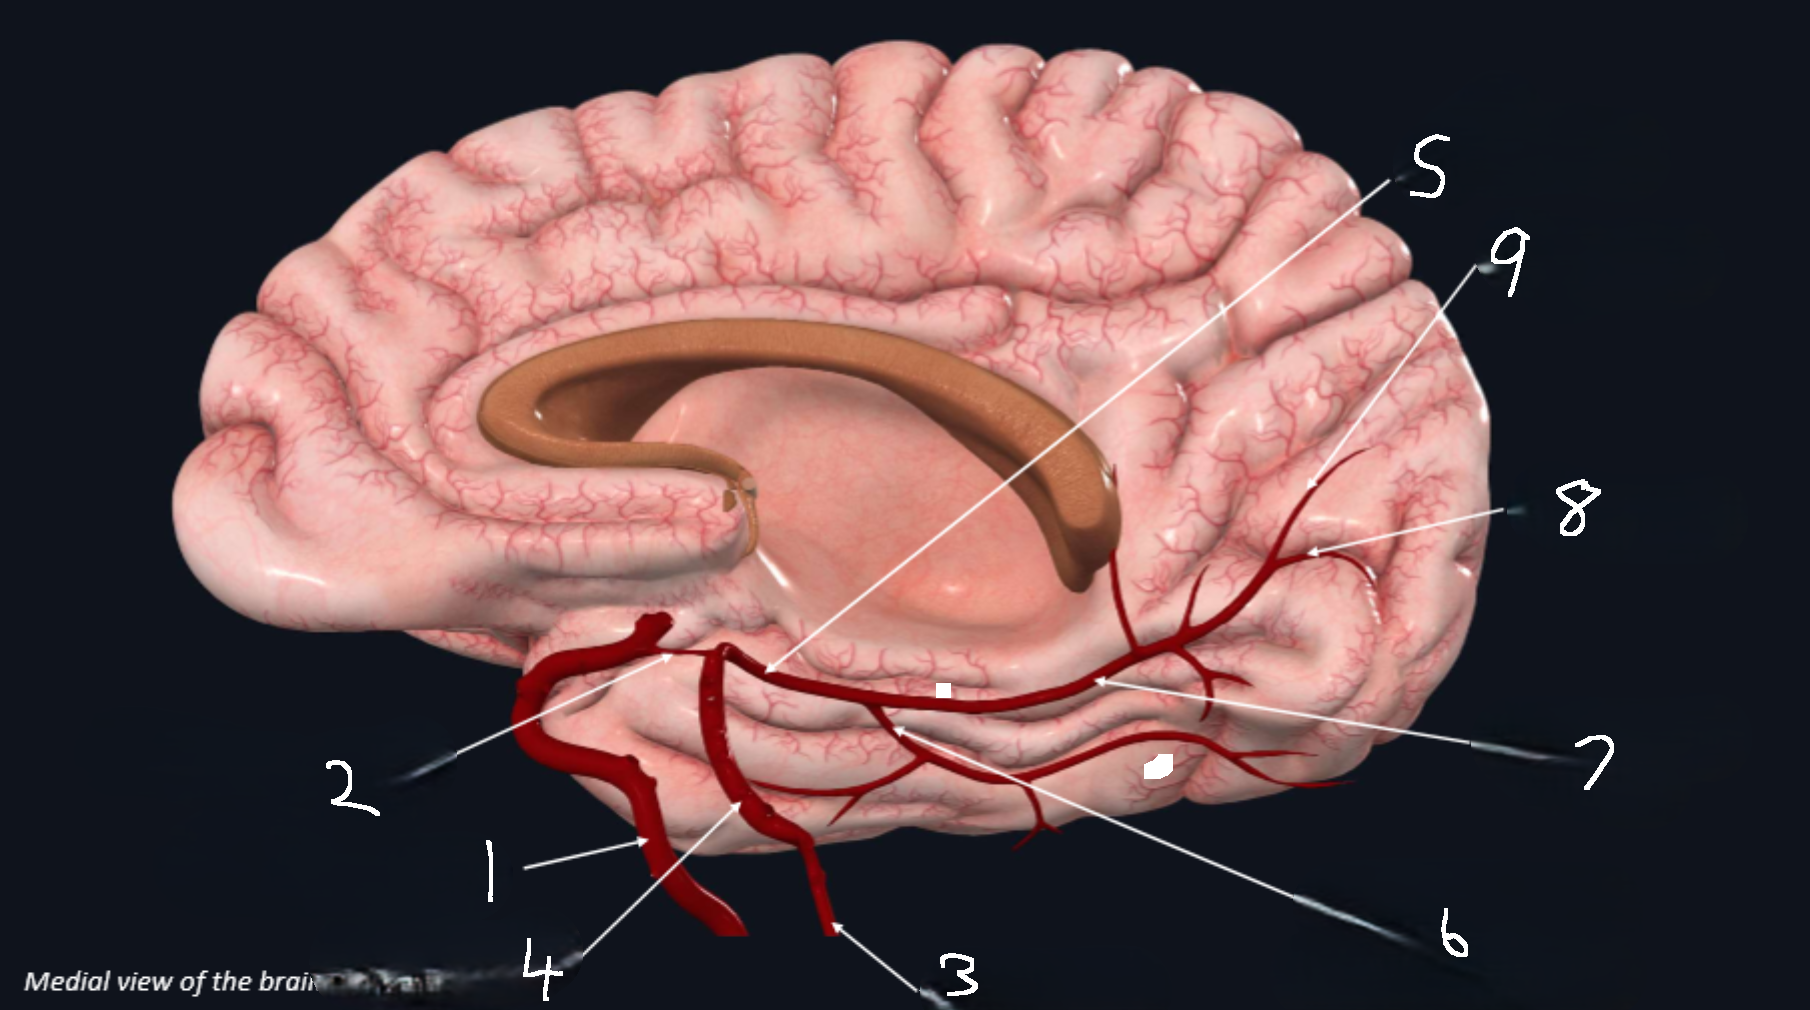

What is 1?

internal carotid artery

What is 2?

anterior cerebral artery

What is 3?

frontopolar artery

What is 4?

pericallosal artery

What is 5?

callosomarginal artery

What is 6?

corpus callosum